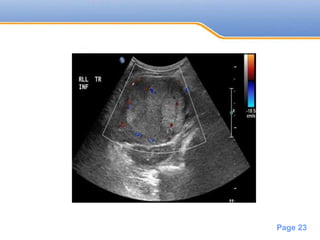

Ultrasound

• Variable appearance

• Small <3cm usually hypoechoic

• Larger tumors often are heterogeneous

• May invade the portal vein

• Most tumors will show central vascularity

on Doppler study

• #23 Well defined low echogenicity mass in segment 4 of the liver, with peri and intralesional vascularity